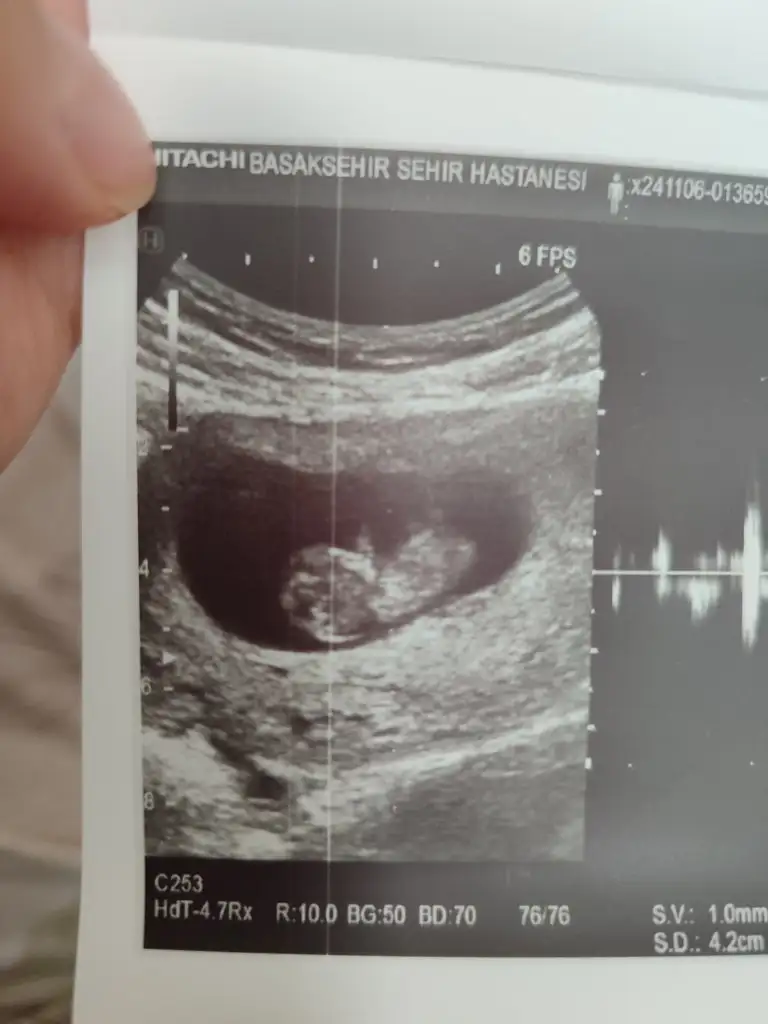

Ben bir şey sormak istiyorum. Siz benden önde olduğunuz için daha tecrübelisinizdir. Sat 26 Eylül haziran sonu temmuz başı doğum gözüküyor. Bugün tam 7.haftamız devlet hastanesinde karından ultrason ile bebeği zor gördü ve kalp atışını dinletmedi 4 mm dedi. Ben hem devlet hem özel takipli gidiyorum geçen hafta 6+2 de özelde alttan bebek gözüktü kalp atışını duyduk bebek o zaman da 4 mm di. Sorum şu karından ve altttan bakıldığında ve cihazlara göre bu farklılık olur mu yoksa bebek gelişmemiş mi sizce cumartesi özelde de kontrolüm var ama içim içimi yiyor. Bu arada devlet şu an 6+1 dedi